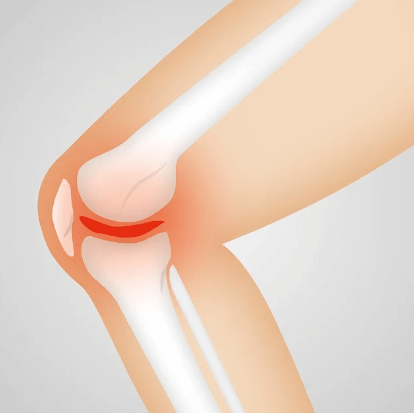

6) 골관절염 진행 억제

연구에 따르면, 골관절염의 진행을 늦추는 데 도움이 될 수 있다고 합니다. 이는 연골 손상을 최소화하고, 장기적으로 관절의 건강을 유지하는 데 기여한답니다.

관절 내 마찰을 줄이고, 연골 사이의 충격 흡수 능력을 높여주기 때문이며 특히나 장시간 서 있거나 앉아 일해야 하는 분들에게 이 성분은 일상 속 불편함을 줄여주는 효과적인 해결책이 될 수 있다고 합니다.

이는 관절염을 포함한 다양한 염증성 질환에서 관절의 붓기와 불편함을 줄여줌으로써, 일상 생활에서의 편안함을 높여줍니다.